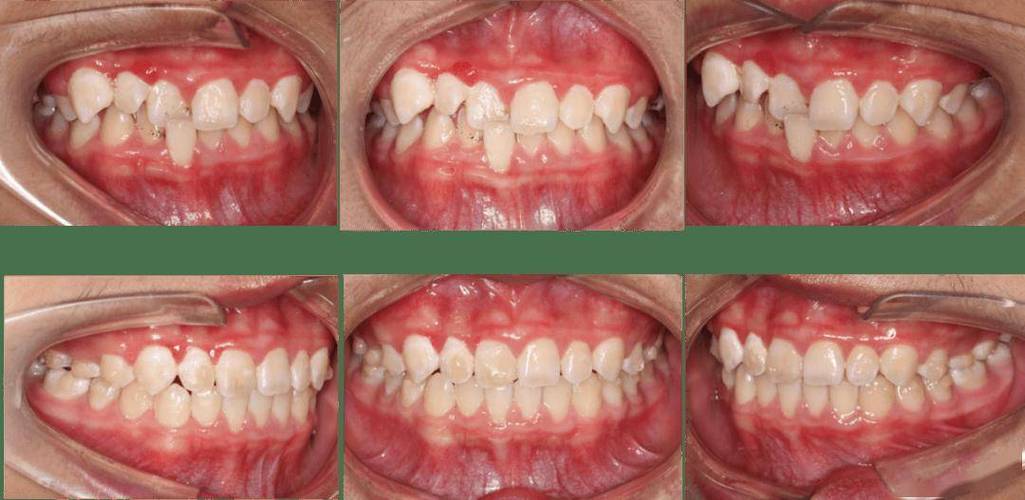

正畸治疗中提到的“3号牙”和“4号牙”重叠,通常指的是上颌或下颌的侧切牙(3号)和尖牙(4号)在牙弓内发生了位置上的重叠或交错排列,这是正畸临床上比较常见的牙齿排列问题之一。

- 尖牙(4号)位于侧切牙(3号)的唇侧(靠近嘴唇)或舌侧(靠近舌头): 这是最常见的重叠类型,尖牙没有正常排列在侧切牙的后方,而是跑到了侧切牙的前面(唇侧)或后面(舌侧),导致侧切牙被“挡住”或“挤到”了不正常的位置。

- 视觉表现: 拍X光片(特别是全景片)或口内检查时,可以清晰地看到这两颗牙齿在牙槽骨内或牙弓上的位置是交错的,而不是一前一后排列。

- 影响美观: 尖牙是“眼尖牙”,其位置异常(尤其是唇侧萌出)会非常明显地影响前牙区的美观和笑容。